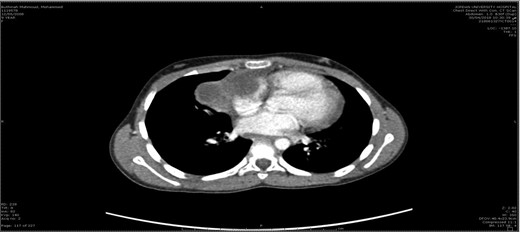

A 10-year-old female patient was well prior to an evaluation for chest pain of two weeks duration, at which an anterior mediastinal mass, was noted on chest radiograph. Chest X-ray (Fig. 1) showed a well-defined homogenous opacity in the right upper and mid zones extending from mediastinum and obliterating the hilar shadow. Transthoracic echocardiography revealed a pericardial effusion. Chest CT (Fig. 2) revealed a well-defined tumor mass involving the anterior mediastinum adjacent to the heart measuring 6 × 4 cm. Mild amount of pericardial fluid noted.

Teratoma is a rare type of germ cell tumor that arises from immature primordial germ cells and can be localized either in the gonads or in an extra-gonadal position, at or near the midline. It originates from two to three germ cell layers. The accepted theory is that they arise from an error in migration of a multipotent germ cell along the urogenital ridge to the gonad during early embryogenesis [2]. The most common reported site for extragonadal teratoma is the anterior mediastinum [3]. Histologically, it is classified as mature; immature; teratoma with malignant transformation; seminoma; and nonseminoma. The patient in our case had mature cystic teratoma located in the anterior mediastinum. Mediastinal mature teratoma is a benign, slow growing neoplasm. The incidence of teratoma worldwide is 1 in 4000 live births [4]. The common age of presentation is young adults with mean age of 20–40 years old. This case uniquely illustrates a very young patient of 10-year-old. Most patients with mediastinal mature teratoma are asymptomatic and in this case the tumor was found incidentally on a chest x-ray. When symptoms are present, it is due to the compression of surrounding structures. These include chest pain, dyspnea, cough and respiratory distress. Occasionally the tumor can rupture and erode into the tracheobronchial tree, pericardium or pleural space, subsequently causing hemoptysis and trichoptysis which is pathognomonic for teratoma [5]. This results in significant complications. In the case being discussed, the patient had a history of left-sided chest pain and heaviness, without cough or dyspnea. The patient had unusual presentation in the form of pericardial effusion and this is an extremely rare consequence of ruptured teratoma. Chest CT is the imaging technique of choice in the evaluation of the abnormal mediastinum. It shows the location and extension of the mass in relation to the adjacent structure as well as to detect hypervascularization of the mass. The typical appearance is heterogenous, sharply marginated, lobulated neoplasms and intrinsic elements of the lesion, including soft tissue, fat, areas of cystic calcifications, and fat fluid which is pathognomonic for diagnosing teratoma [6]. It can also show findings of ruptured teratoma, which consist of heterogeneity of the mass, fat globules at the rupture site, consolidation or atelectasis in the adjacent lung, and effusion. In comparison to our case, the CT scan shows multiloculated pericardial cysts containing yellowish sebaceous materials. A chest X-Ray typically reveals a rounded, well-circumscribed, lobulated calcification protruding against the adjacent lung. This combination of findings is consistent with our case. Visualizations of well-formed tissues such as teeth and hair are pathognomonic. MRI is useful to further evaluate the mass infiltration. It will reveal the heterogenous signal intensity containing mixtures of fat, water, soft tissue, and calcifications. Fortunately for this patient, no invasions of adjacent structures were found. Hence, no complication ensues. CT-guided biopsies are usually done to determine whether the tumor was malignant or benign. The diagnostic biopsy, either by thoracoscopic or open surgery, may be indicated to determine the specific germ cell tumor. Therefore, open surgery through median setrnotomy was done on the patient and we found it was a ruptured cystic teratoma with inflammatory reaction without any elements of immaturity or malignancy. Involvement of pericardium is considered a life-threatening condition which emphasizes the need for urgent intervention. Complete surgical excision is the treatment of choice for mediastinal teratoma. It helps in establishing the diagnosis as well as ensuring a long-term cure rate with little chance of recurrence. The most commonly performed method is median sternotomy due to excellent exposure. If it affects the hemithorax, lateral thoracotomy is selected instead [7]. In malignant teratoma, combination with chemotherapy can improve survival [1]. Median sternotomy is the surgical approach of choice for this case. Since mature teratomas are benign tumors, it has excellent prognosis.